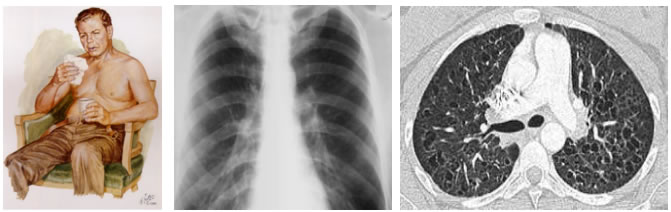

- RASGOS OBSERVABLES FÍSICAS Y RADIOLÓGICAS DE ESTOS PACIENTES:

BRONQUITIS CRONICA: tos y expectoración por más de 3 meses y por más 2 años consecutivos.

Figura 1. Blue bloater, actualización de la guía española para el manejo de la EPOC ( GesEPOC2017)

Figura 2. Manual MSD

Figura 3. Actualización de la enfermedad pulmonar obstructiva crónica: claves clínicas y hallazgos radiológicos en tomografía computarizada por Felipe Aluja Jaramillo, Juan Andrés Mora Salazar. 2018

- Bronquitis crónica: tos, disnea, expectoraciones blanquecinas en la etapa incipiente que se asocia con dificultad respiratoria al esfuerzo que se desarrolla de manera progresiva con el tiempo, convirtiendo al paciente en discapacitado respiratorio. A medida que se exponen más al humo de tabaco su situación clínica empeora llegando a crecimiento de corazón derecho, congestión vascular y hepatomegalia, así como edema de extremidades. Con una gasometría con oxigeno bajo, aumento de co2.

- Bronquitis crónica: roncus y sibilancias, mucha tos con roco persistente, aumento de trama bronco vascular en la radiografía y tomografía.